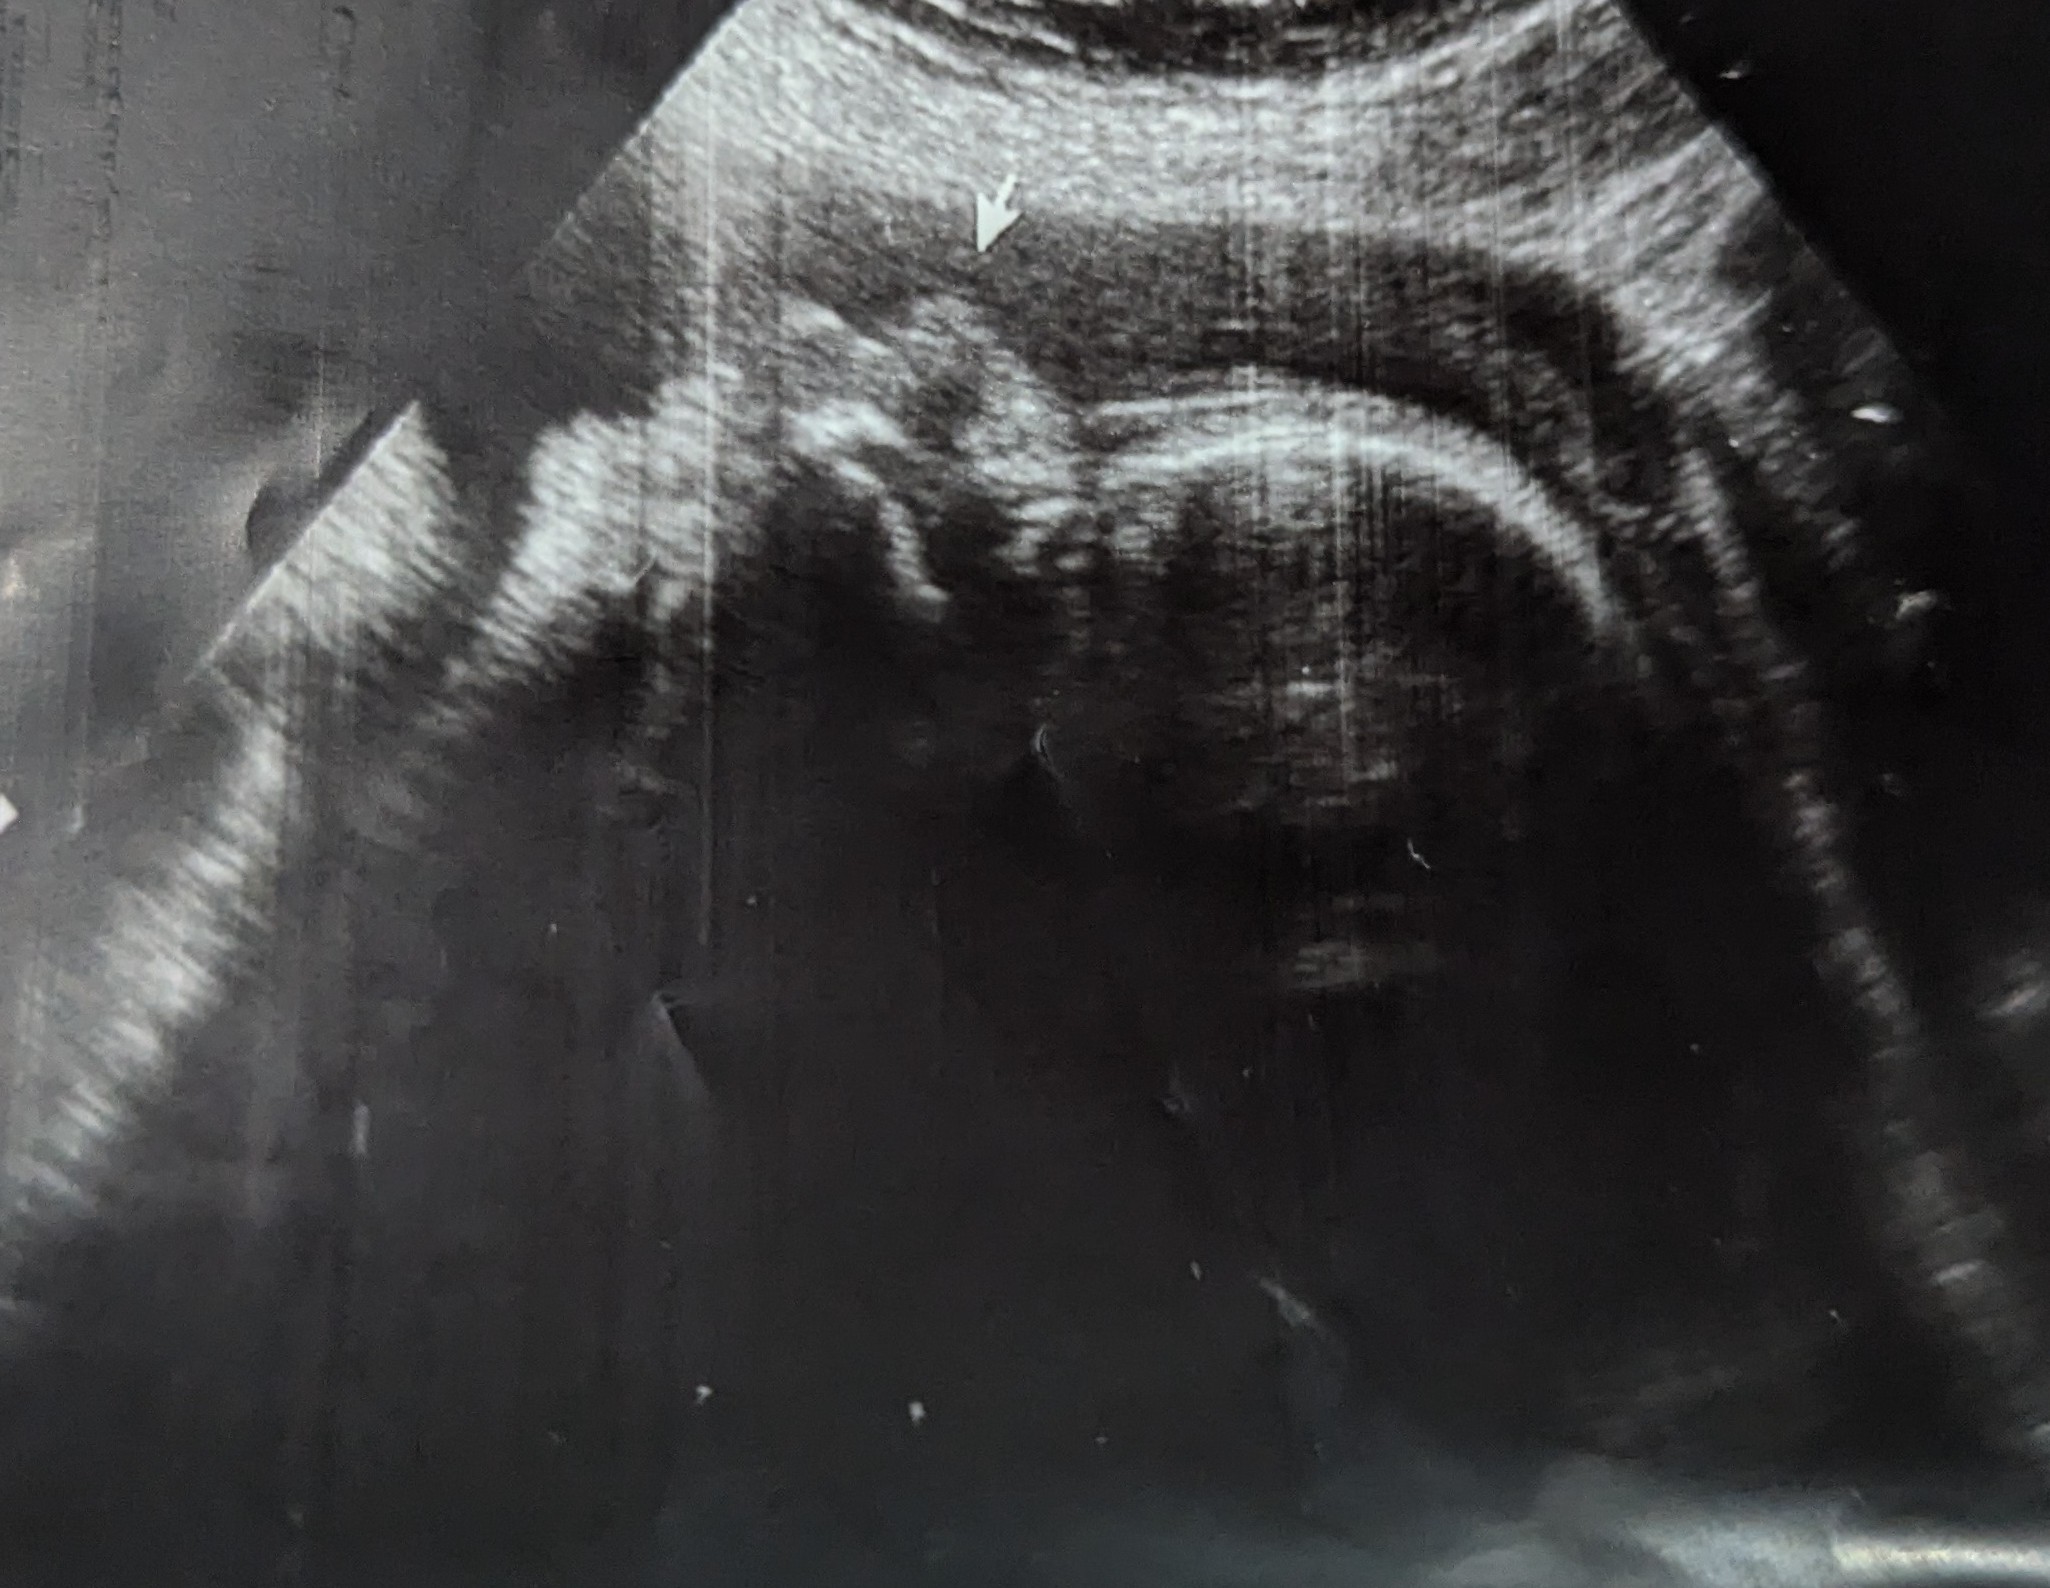

Leie: Free floating, i går lå han helt tydelig på tvers, i dag er jeg litt usikker men muligens ligger han med hodet ned.